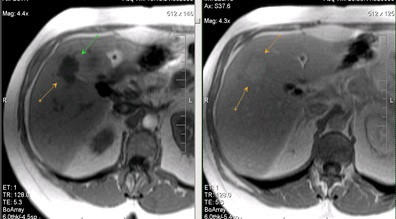

Egyedi kis májáttétek; hasonlóság a natív vizsgálat hemangiomas.

Ugyanez a beteg. Postkontrastnye tomográfia. Egyedi kis májmetasztázisok ellentétben hemangiomas tomogramjait a korai és a késői fázisban válik parenchymás hypointense a natív vizsgálat (gyors enyhülést kontraszt kritérium 1 perc).

Áttétek a májban, a jobb vesét.